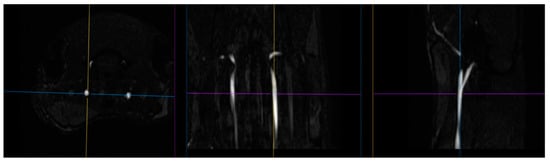

4.4. Magnetic Resonance Angiography

The blood supply of the brain was examined using time of flight (TOF) angiography in one scan session with MRI [56,57]. Images of the common carotid arteries (left and right; Figure 14) were obtained in a two-dimensional projection (an example is shown in Figure 15), which, by means of the ParaVision5.1 MIP (maximum intensity projection) option, were converted into 3D images. The measurement of the size of the vessels was performed using an ROI placed 2 mm proximal to the bifurcations of the carotid arteries, which were determined from 3D images. Along with the imaging of angioarchitectonics, the blood flow velocity was assessed by the method of phase contrast angiography PCA (phase contrast angiography). The measurement was performed in a single cross-sectional main blood flow section, also guided by a 3D model (an example of PCA phase contrast angiography is shown in Figure 2). We performed these measurements 2 mm proximal to the bifurcations of the carotid arteries, that is, in full accordance with the area of measurement of dimensions of the vessels’ lumen. Additionally, the maximum blood flow velocity in the central part of the artery and the average linear blood flow velocity for the entire section of the lumen of the artery were determined. Volumetric blood flow (mL/min) was calculated based on the mean blood flow velocity and cross-section. All hemodynamic characteristics were obtained in a 2 min recording interval with averaged values as a result of several complete heartbeat cycles. The following indicators were used in the paper: the speed of blood flow in the left and right common carotid arteries (velocity of OSA L, cm/s; velocity of OSA P, cm/s); the area of the lumen of the left and right common carotid arteries (lumen o.s.a. L, mm2; lumen o.s.a. P, mm2); volumetric blood flow of the left/right common carotid artery and their sum score (o.s.a. blood flow L, mL/min; o.s.a. P blood flow, mL/min; o.s.a. blood flow, mL/min).

Figure 14. The images of the carotid arteries in three projections (in order to select the area of blood flow assessment).